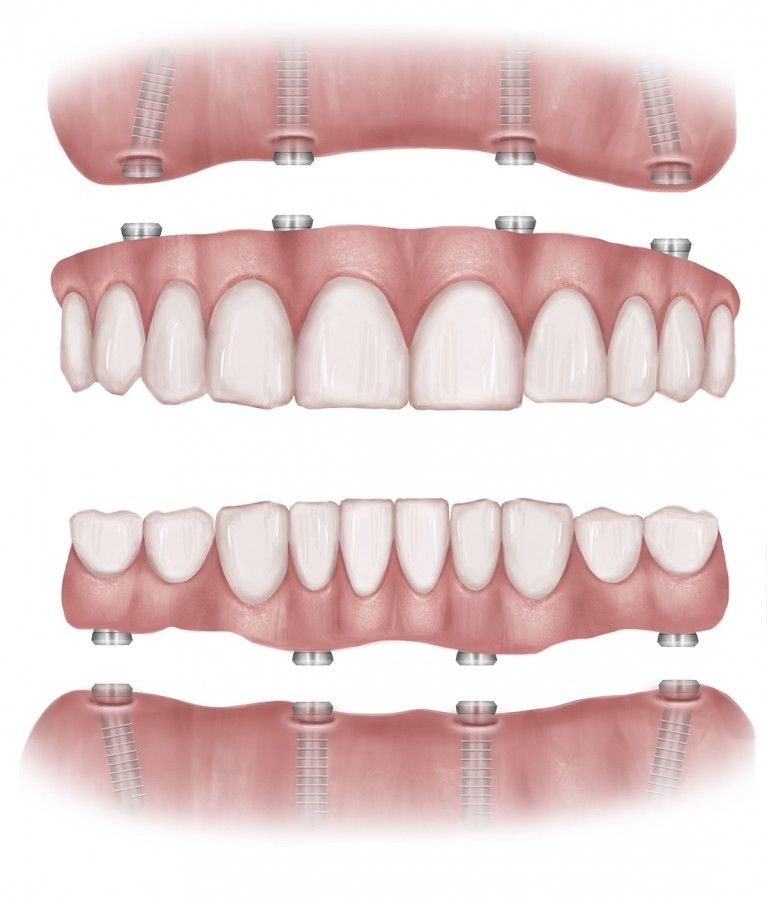

Full Arch – Same Day Teeth | Dental implants Leeds, Infinity Dental Clinic

Same Day Teeth | Dental Implants Leeds | Infinity Dental Clinic

Same Day Teeth | Dental Implants Leeds | Infinity Dental Clinic

All-on-6 Dental Implants in Turkey | The BEST 12 clinics Prices 2020

All On 4 Dental Implants Kent | All-on-4 cost Fr £1.70 P/D Same Day Teeth

All Teeth On 4 Dental Implants Sydney | Full Mouth Fixed Dental …

The Complete Guide to the All-on-4 Dental Implant Procedure